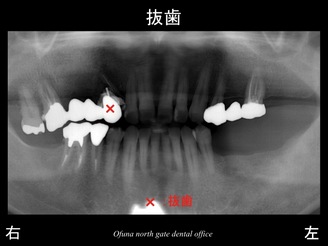

スライド05

下顎の左側の奥歯がかなり以前から欠損していました。

そのため、食事のほとんどを右側で食べることになっていました。

ところが、少し前から上顎の左側の奥歯で噛むことができなくなってきました。

上顎左側が歯根破折 していたのです。

スライド06

歯根破折 している場合、抜歯となることがほとんどです。